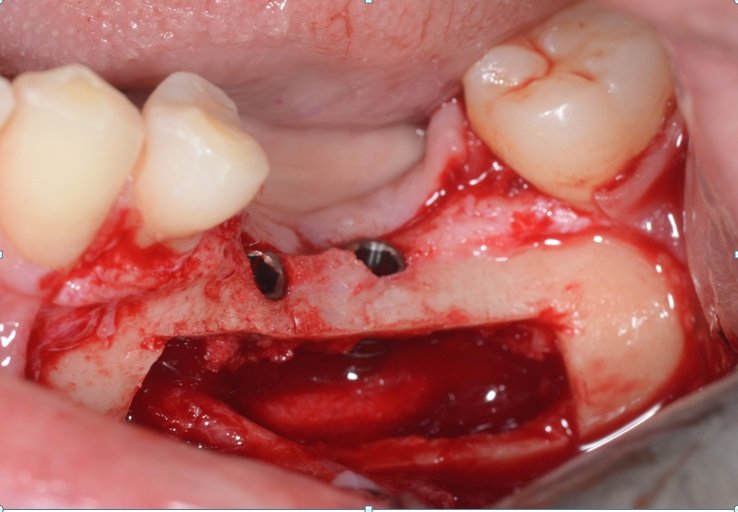

Remoção do osso vestibular com um cinzel curvo para ter acesso ao nervo alveolar (Fig 7).

Osteotomia óssea ao redor do foramen mentoniano para liberação total do nervo.

Depois da remoção do bloco ósseo retiramos o osso medular com curetas de Lucas ou molt até a completa visualização do nervo alveolar.

Colocação do guia cirúrgico e marcação do local ideal dos implantes.

Descolamento do nervo alveolar, deixando-o solto dentro do canal. Podemos colocar um túnel check ou fresa deslocando o nervo para o lado em um dos alvéolos artificiais enquanto terminamos a fresagem e colocamos os implantes.